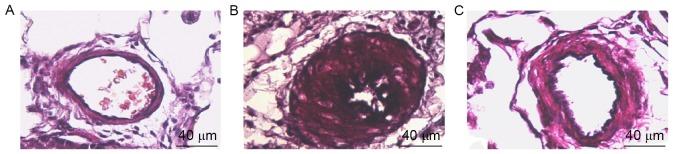

The aim of the present study was to investigate the effects of paclitaxel (PTX), at a non-cytotoxic concentration, on pulmonary vascular remodeling (PVR) in rats with pulmonary hypertension (PAH), and to explore the mechanisms underlying the PTX-mediated reversal of PVR in PAH. A total of 36 rats were divided into control group (n=12), model group (n=12) receiving a subcutaneous injection of monocrotaline (60 mg/kg) in the back on day 7 following left pneumonectomy and PTX group (n=12) with PTX (2 mg/kg) injection via the caudal vein 3 weeks following establishing the model. The degree of PVR among all groups, as well as the expression levels of Ki67, p27 and cyclin B1, were compared. The mean pulmonary artery pressure, right ventricular hypertrophy index [right ventricle/(left ventricle + septum) ratio] and the thickness of the pulmonary arterial tunica media in the model group were 58.34±2.01 mmHg, 0.64±0.046 and 65.3±3.3%, respectively, which were significantly higher when compared with 23.30±1.14 mmHg, 0.32±0.028 and 16.2±1.3% in the control group, respectively (P<0.01). The mean pulmonary artery pressure, right ventricular hypertrophy index and thickness of the pulmonary arterial tunica media in the PTX group were 42.35±1.53 mmHg, 0.44±0.029 and 40.5±2.6%, respectively, which were significantly lower when compared with the model group (P<0.01). Compared with the control group, the expression levels of Ki67 and cyclin B1 in the model group were significantly increased (P<0.01), while p27 expression was significantly reduced (P<0.01). Following PTX intervention, the expression levels of Ki67 and cyclin B1 were significantly reduced when compared with the model group (P<0.01), while p27 expression was significantly increased (P<0.01). The results of the present study suggest that PTX, administered at a non-cytotoxic concentration, may reduce PAH in rats, and prevent the effects of PVR in PAH. These effects of PTX may be associated with increased expression of p27 and decreased expression of cyclin B1.